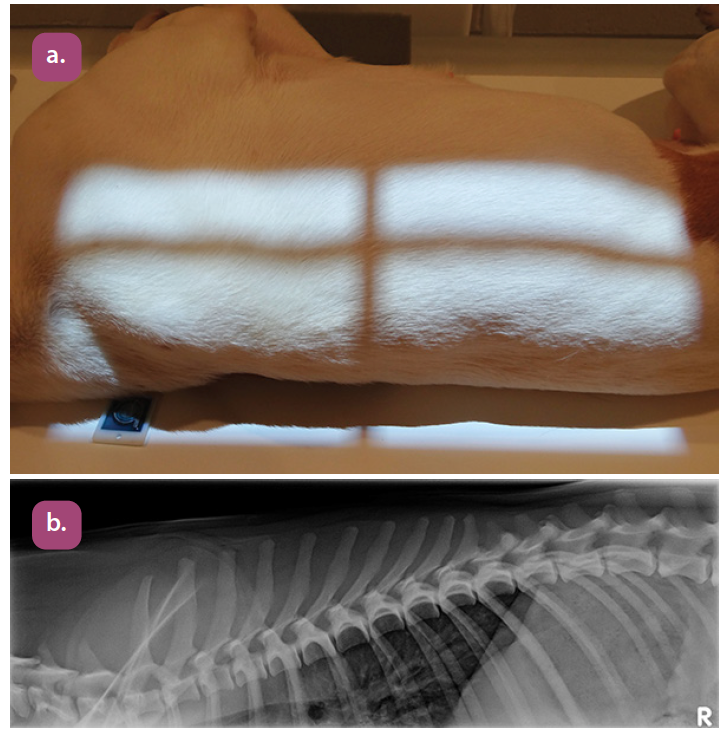

lateral thoracic spine projection

lateral thoracolumbar spine projection